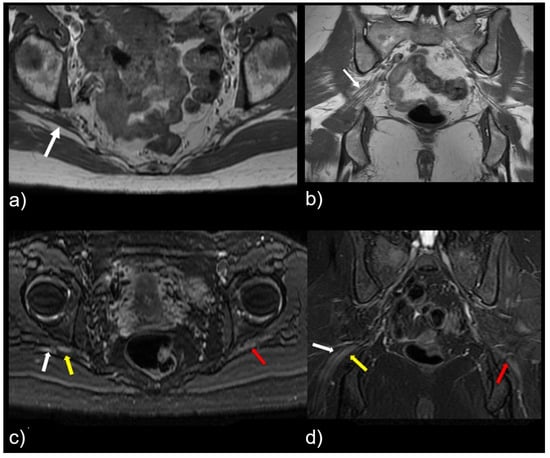

Figure 4.

Patient with a symptomatic type II variant and a split right sciatic nerve. Axial (a) coronal (b) T1-weighted sequence, showing the two components of the split sciatic nerve (white arrow). Axial (c) and coronal (d) T2-weighted IDEAL sequences demonstrate the split sciatic nerve, with the common peroneal (white arrow) and the tibial (yellow arrow) nerve components seen distinctively. There is also increased nerve caliber and increased nerve T2 signal involving the split right sciatic nerve, relative to the normal caliber and T2 signal of the left sciatic nerve (red arrow).

This study shows that variant sciatic nerve anatomy in relation to the piriformis muscle can be identified by MR neurography, and is more likely to be associated with nerve signal changes and corresponding symptomatology. R egardless of the variant sciatic nerve type, imaging findings that strongly correlated with the symptomatic side are abnormal nerve T2 signal, increased nerve caliber, and asymmetric piriformis size (Figure 4). Variant sciatic nerve anatomy may occur in up to 13% of the population [6,17] and can be difficult to identify without advanced imaging, such as MR neurography. Variant sciatic nerve anatomy may therefore represent an under-diagnosed cause of extraspinal sciatica and piriformis syndrome. To our knowledge, prior studies have not evaluated the imaging prevalence of these variants on MR neurography and their clinical implications.

Variant sciatic nerve anatomy also showed a statistically significant (p = 0.01) increased rate of T2-signal abnormality (63.0% variant vs. 43.0% normal). In both groups, the signal abnormality occurred at, or just distal to, the greater sciatic foramen, possibly reflecting the most vulnerable site for nerve entrapment or compression. Furthermore, regardless of variant sciatic nerve type, increased nerve T2 signal strongly correlated with the symptomatic side (98.0%). Figure 5 illustrates this finding, with bilateral type II variant split sciatic nerves in a patient who presented with symptoms on the left side, wherein increased signal was demonstrated only on the left (symptomatic) side. Although only a minority of variant and normal nerves displayed an asymmetric nerve caliber or asymmetric piriformis size (hypertrophy or atrophy), both imaging findings were significantly associated with the symptomatic side (98.0%). A detailed evaluation of variant anatomy is therefore essential for an accurate diagnosis.